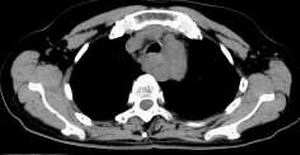

女,61岁,吞咽困难(包括开水)已久。

食道中上段癌并锁骨上窝淋巴结转移.

食道中上段中分化鳞癌伴锁骨上淋巴结转移